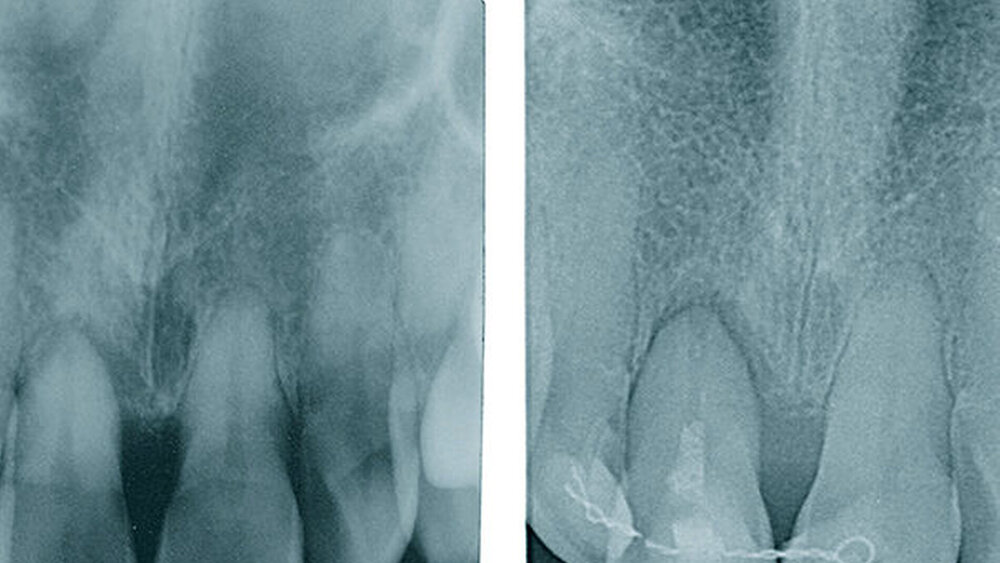

Seit rund einem halben Jahr testen Sie die neue PROGRESSIVE-LINE. Was sind die Hauptindikationen?Hermann:Im Juni 2018 haben wir in unserer Praxis in Zusammenarbeit mit der Abteilung R&D (Forschung & Entwicklung) von CAMLOG mit der klinischen Dokumentationsphase des CAMLOG PROGRESSIVE-LINE Implantats begonnen. Bis dato haben wir zirka 80 Implantate bei einer ausgewogenen Verteilung in Bezug auf verschiedene klinische Indikationen dokumentiert. Die Dokumentation des neuen Implantatsystems erfolgte im Hinblick auf die erzielte Primärstabilität in Abhängigkeit von der Knochenqualität (dies wurde mit der Chirurgieeinheit iCHIRO-PRO durchgeführt) und die Verlaufskontrolle der knöchernen Stabilität des Implantats mit dem Osstell-ISQ. Zudem wurde anhand eines Beobachtungs- und Dokumentationsbogens relevante Parameter während der Einheilungsphase erfasst. Momentan befindet sich die Hälfte der Implantate schon in der postprothetischen Dokumentationsphase. Unsere Erfahrungen in Bezug auf eine sicher zu erzielende Primärstabilität und eine zuverlässige Osseointegration sind durchweg positiv.

In welchen klinischen Anwendungen bietet das Implantat Vorteile?Hermann:Das neue CAMLOG PROGRESSIVE-LINE Implantat besticht durch sein innovatives parallel-konisches Makrodesign mit einem speziellen Gewinde, bei gleichzeitig bewährter Prothetikschnittstelle der Camlog-Linie. Dies bedeutet, dass in der chirurgischen Phase mit diesem Implantat eine zuverlässige Primärstabilität erzielt werden kann, speziell bei schwierigen anatomischen Voraussetzungen, wie z. B. bei der Sofortimplantation, bei reduzierter Kieferkammbreite oder konkav verlaufenden Alveoloarkämmen sowie bei weichem Knochen im Oberkiefer. Aufgrund des krestalen Verankerungsgewindes sehen wir zudem einen Vorteil bei der Platzierung des Implantats im Zusammenhang mit einer simultanen, offenen Sinusbodenelevation bei stark reduzierter Restknochenhöhe (2–3 mm). Auch einzeitige Verfahren lassen sich einfacher durchführen. Denn auch im kompromittierten Knochen erreicht das Implantat eine hohe vorhersagbare Primärstabilität.

Ihr Fazit? Hermann:Zusammenfassend kann ich sagen, dass wir mit der CAMLOG PROGRESSIVE-LINE eine Erweiterung der klinischen Indikationen in Bezug auf eine simultane Vorgehensweise (Implantation und Augmentation kombiniert) beobachtet haben, und zwar aufgrund der bereits erwähnten Primärstabilität bei schwierigen anatomischen Situationen. So können wir in vielen Fällen auch eine Sofortversorgung/Sofortbelastung des Implantats in Erwägung ziehen. Die situative Adaptation des Bohrprotokolls verschafft uns eine effiziente Insertion, die vorhandene, bewährte Prothetikschnittstelle der Implantate von CAMLOG das vertraute Handling, und dies alles bei einem Implantat, das wir bei allen klinischen Situationen zum Einsatz bringen konnten.